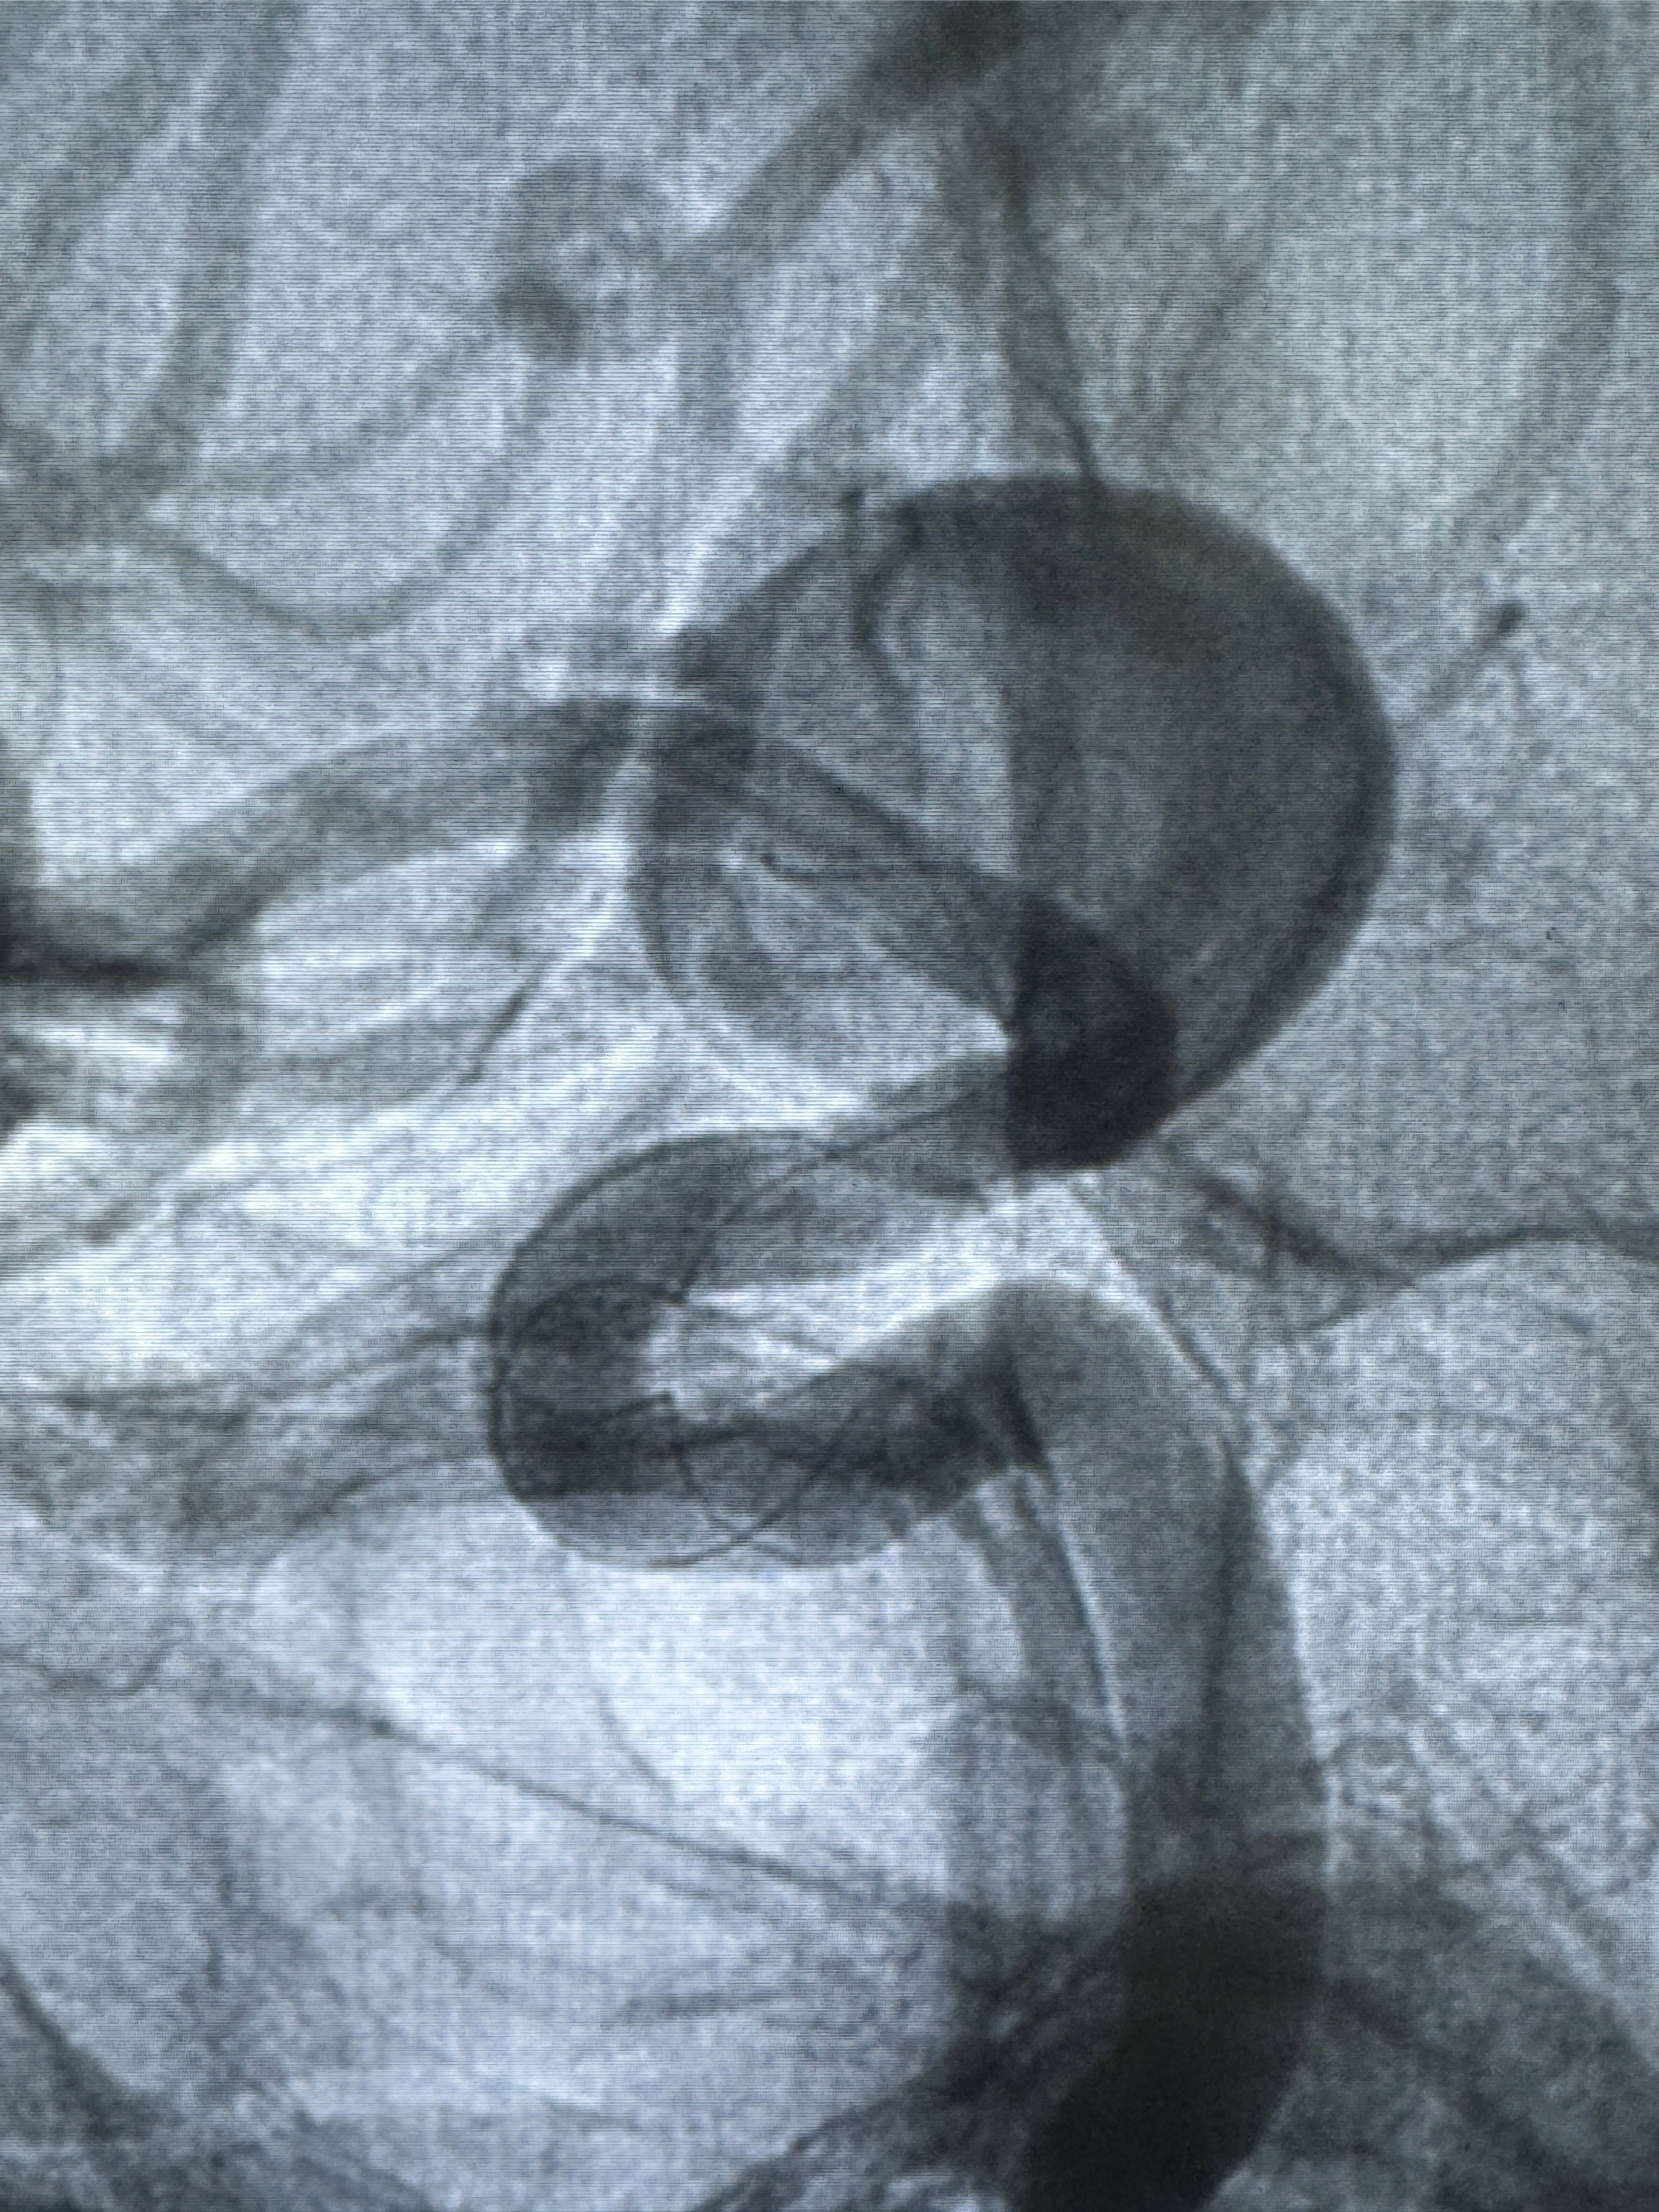

4.5-30mmTurbridge密网支架,于M1近心端打开

透视下支架释放满意

多角度显示支架打开情况

造影显示支架贴壁情况

再次造影确认支架贴壁情况

支架植入顺利,贴壁佳,支架内血流通畅,动脉瘤内血液滞留明显